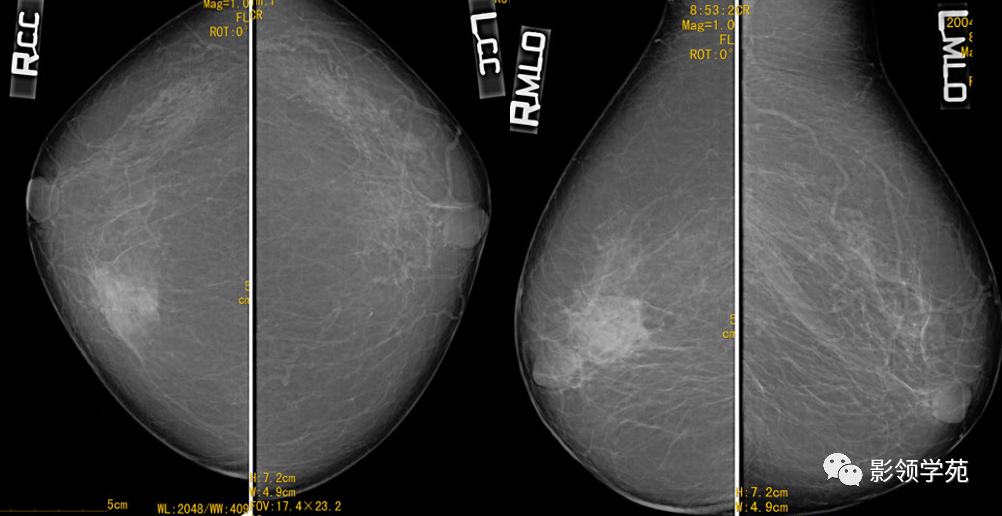

右乳腺内象限见一团片状致密影,边缘尚清,内未见明确钙化;皮肤、乳头未见异常,未见肿大淋巴结影。

手术病理:(右乳腺)导管乳头状瘤病,导管上皮伴中-重度非典型增生。